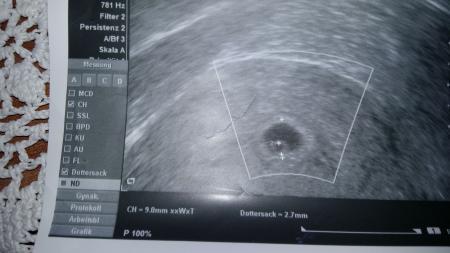

Bin jetzt 6ssw+3 TAGE UND NUR DAS ZUSEHEN KANN ICH NOCH HOFFNUNG HABEN

was sagte denn der FA? Dottersack ist zu sehen und das ist ne embryonale Anlage. vielleicht ist die SS einfach etwas jünger.. Fruchtblase ist auch rund und nciht unförmig eingefallen. hoffen kannst du sicher immer.. manchmal sieht man eben erst sehr viel später was.. kann man leider NIE so pauschal sagen, sondern ist immer individuell aber sieht doch gar nicht os schlecht aus? oder warum hast du solche Sorge?

Im kh sagten man müsste schön mehr sehen der Rest wächst auch

Für 6+3 ist es tatsächlich etwas wenig. Sieht eher nach 5+2 oder so aus. Kann es sein, dass der Eisprung später war als du vermutest?

Hallo, . Nach deiner eigenen Aussage bei Bitte noch ein Baby zu deinem Zyklus kann deine ss durchaus jünger sein. Und ich finde man sieht was man sehen sollte. Bei meinem zweiten sohn war auch nicht mehr zu sehen und die ss angeblich 7 tage jünger bis zur 14ssw war das so dann war er immer 3 tage weiter. Letzten endes wars egal er kam 3 Wochen vorm Termin und alles war gut. Heute ist er 12 Wochen alt. Dir bleibt eh nur abwarten und guter Hoffnung sein. Alles andere liegt nicht in deiner Hand. Lg nita